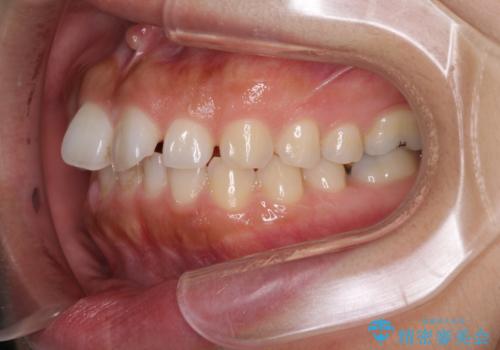

隙間の空いた前歯を閉じたい インビザライン矯正

- 前歯の隙間を気にして来院された患者様です。

隙間、捻転ともに軽微でありましたが、下顎前歯の突き上げにより隙間ができていたため、インビザラインを用いて咬み合わせを改善しながら前歯の歯列を整えていくこととしました。

当初は1年程度で終えられると思いましたが、治療途中から装着時間が短くなったり、来院間隔が長期になったりとし、結果として4年半以上の治療期間となりました。

治療途中に上顎前歯は失活してしまいましたが、変色が顕著ではないため、経過を見ていくこととなりました。